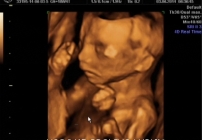

USG 3D i USG 4D w Lublinie w Centrum Medycznym PROVIVO to nowoczesne badania ultrasonograficzne, które pozwalają dokładnie ocenić rozwój płodu, a jednocześnie dają przyszłym rodzicom możliwość zobaczenia dziecka w znacznie bardziej realistyczny sposób niż podczas klasycznego badania 2D.

Badanie USG 3D/4D pozwala nie tylko na ocenę wybranych struktur i rozwoju ciąży, ale również na podgląd twarzy dziecka, jego ruchów oraz mimiki. To połączenie wartości diagnostycznej i wyjątkowego doświadczenia dla przyszłych rodziców.

Badanie USG 3D/4D w Lublinie umożliwia dokładny wgląd w rozwój płodu i pozwala zobaczyć dziecko w sposób zbliżony do jego aktualnego wyglądu. W porównaniu do klasycznego badania USG 2D obraz jest bardziej realistyczny i czytelny dla rodziców.

USG 3D daje możliwość trójwymiarowej rekonstrukcji obrazu płodu oraz wnętrza macicy. Dzięki temu można zobaczyć powierzchnię zewnętrzną ciała dziecka, a twarz płodu staje się znacznie wyraźniejsza niż w klasycznym badaniu 2D. To badanie szczególnie cenione przez rodziców, którzy chcą zobaczyć dziecko jeszcze przed porodem w bardziej realistyczny sposób. Na obecnej stronie PROVIVO wskazano również, że rodzice otrzymują zapis badania w formie elektronicznej.